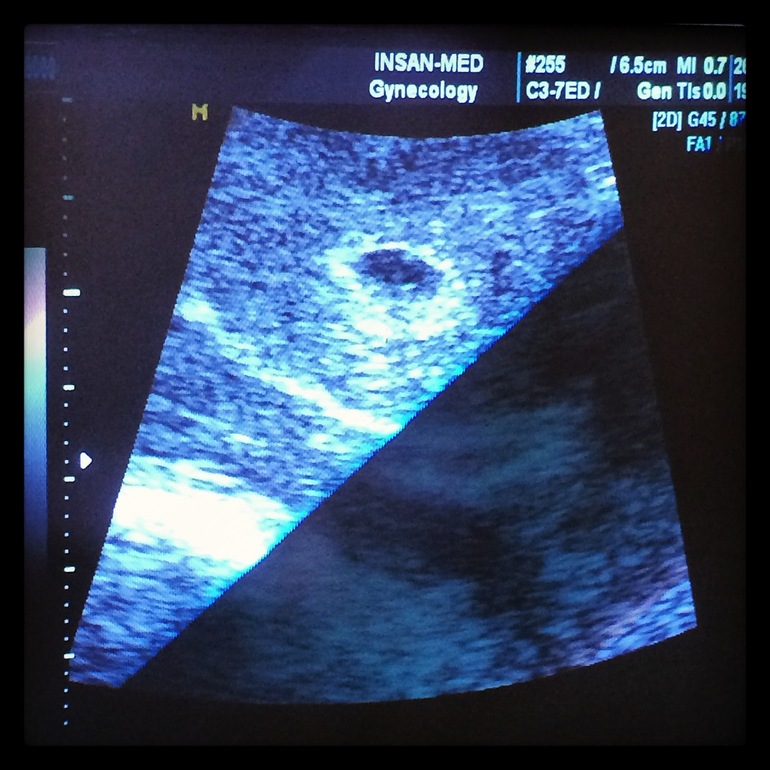

В общем, пошла я на УЗИ в платную клинику. Узист мне понравился, хороший такой молодой человек, очень доброжелательный. Сразу показал мне малютку (пока плодное яйцо), улыбался глядя на мою счастливую физиономию)) Сказал что всё хорошо и никакой явной угрозы он не видит, но есть тонус по задней стенке.

Не удержалась - отправила мужу фотографию)) Такой восторг! Он очень радуется, хотя старается не показывать (интроверт жуткий). Вчера весь вечер ходил вокруг меня и говорил "Хочу уже ребёночка!" Так мило))